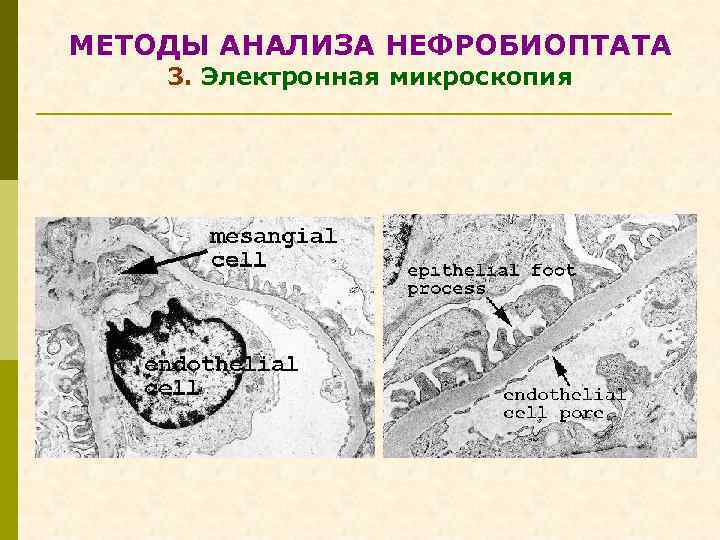

МЕТОДЫ АНАЛИЗА НЕФРОБИОПТАТА 3. Электронная микроскопия